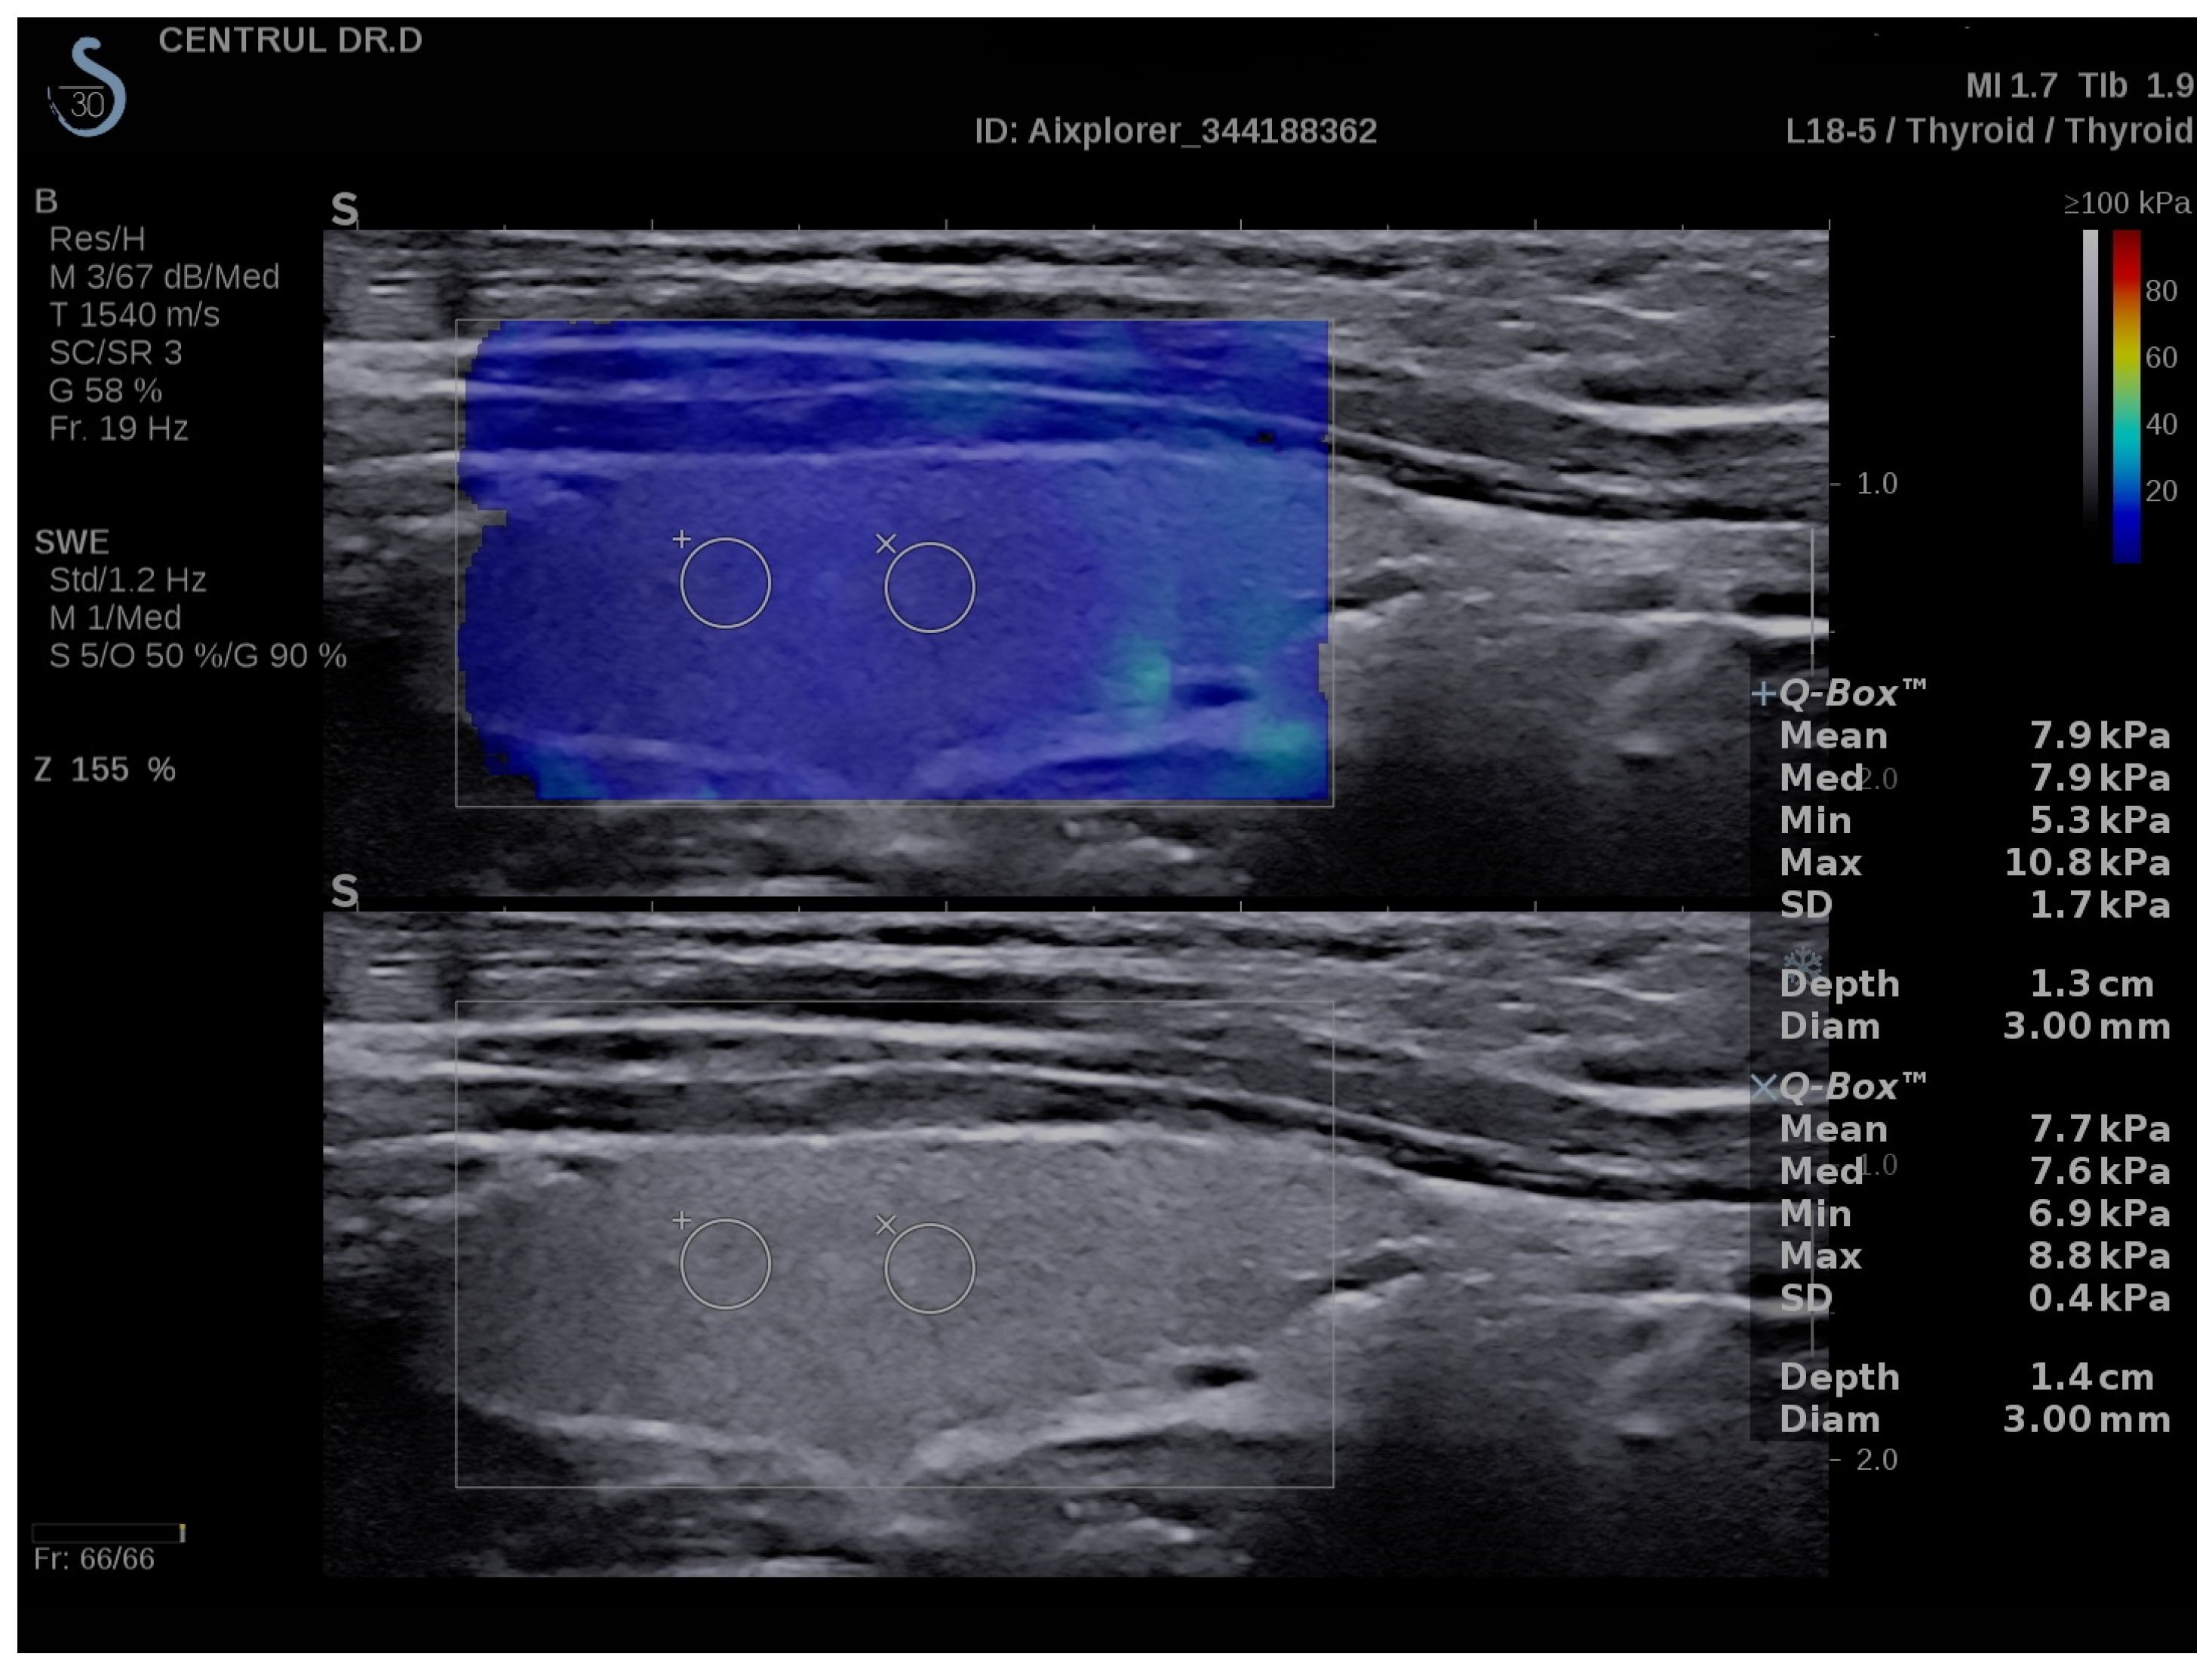

2.4. Conventional Ultrasound and Elastography Examination

3.2. SWE Measurements